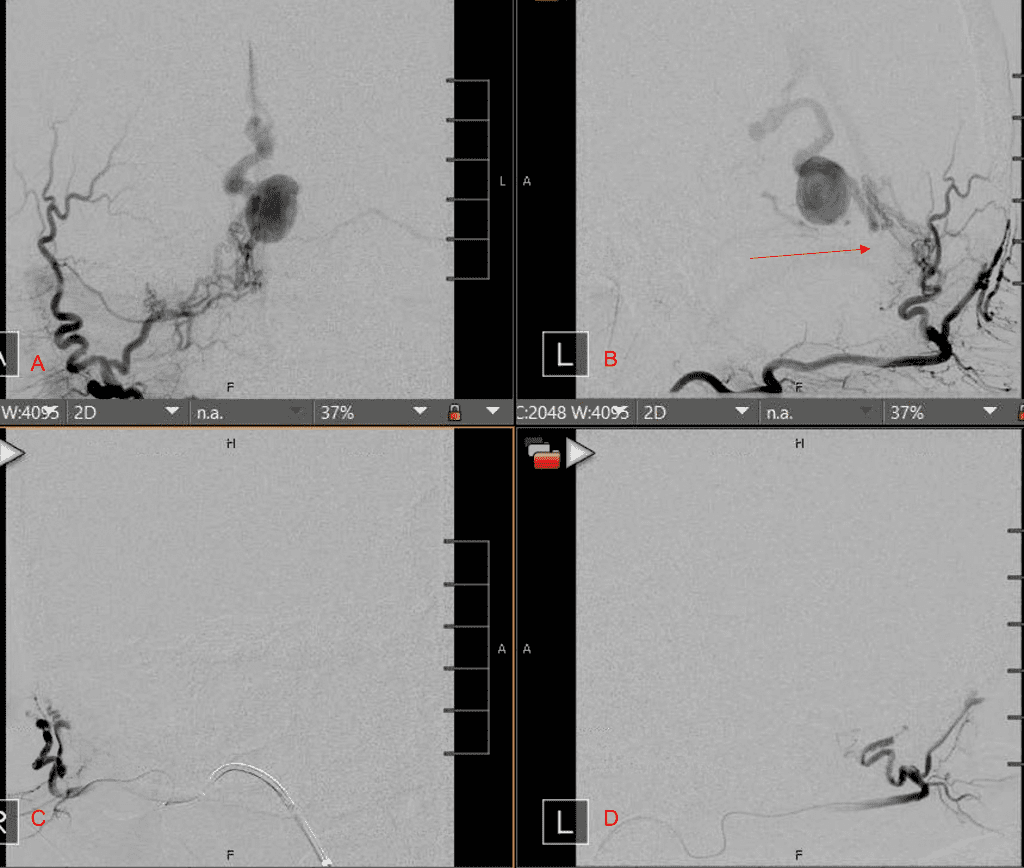

Figure 3. Right ECA AP and Lateral angiograms Pre (A and B) and Post NBCA embolization (C and D) Demonstrate near complete obliteration of right Occipital and Middle Meningeal Artery Fistulas

Figure 4. Left ECA AP and Lateral angiograms Pre (A and B) and Post NBCA embolization (C and D) Demonstrate near complete obliteration of Left Occipital Artery Fistulas.

Embolization was successful at immediately reducing the pressure into the Aneurysmal Varix with greater than 90% reduction in A-V shunts. After an intensive period of critical care monitoring and care for her initial brain hemorrhage, she made a near complete recovery with mild intermittent left sided paresthesias and generalized deconditioning. After receiving inpatient and outpatient Acute Rehabilitation, Physical, and Occupational therapy, she completely recovered all of her Activities of Daily Living (ADLs) at 3 months and achieved an modified Rankin Scale (mRS) of 0. On follow-up angiography, small residual low flow A-V shunts were identified and targeted for Gamma Knife Radiosurgery (Figure 5 and 6).